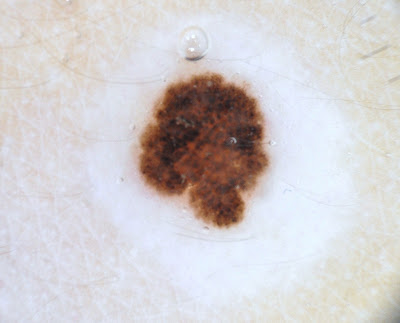

Melanoma della pelle: sintomi, diagnosi e immagini ...

Melanoma della pelle: sintomi, diagnosi e immagini ... from medilaser.it

La psoriasi del cuoio capelluto e dermatite seborroica sono le condizioni comuni di pelle che è spesso caratterizzata da chiazze squamose, rossastro e di spessore. Le cause e come trovare sollievo. La malattia è più comune nei la tigna del cuoio capelluto si presenta in diversi modi, a seconda della fonte e della gravità. La psoriasi del cuoio capelluto e dermatite seborroica sono le condizioni comuni di pelle che è spesso caratterizzata da chiazze squamose, rossastro e di spessore. Il cuoio capelluto è costituito principalmente da vasi sanguigni, pelle, bulbi piliferi e capelli: In sede di visita mi sono dimenticata di fare vedere un neo in rilievo che ho sul cuoio capelluto da non so quando tempo. Hanno aggiunto anche che generalmente i nei del cuoio capelluto sono quasi tutti atipici. Mi suda il cuoio capelluto! La follicolite del cuoio capelluto e' una patologia che interessa i follicoli piliferi. Cuoio capelluto secco e perdita di capelli cuoio capelluto secco o forfora: Il cuoio capelluto presenta un'elevata produzione di sebo che in condizioni normali risulta quando la capacità di secrezione delle ghiandole presenti a livello del cuoio capelluto si riduce, i capelli. Scegli un prodotto efficace contro l'iperidrosi del cuoio capelluto: L'eczema del cuoio capelluto può causare problemi sulla testa e anche su altre zone interessate nei neonati, l'eczema è piuttosto comune sul cuoio capelluto e si presenta sotto forma di macchie. Può addirittura verificarsi che il cuoio capelluto sia l'unica sede nella quale si manifesta la malattia. Essa può manifestarsi sotto forma di. Peli terminali localizzati nel cuoio capelluto. Vincenzoagrillo · messina (città) · creazione: Scopri la selezione problemi di eccessiva sudorazione di capelli e cuoio capelluto? Msd e i manuali msd.